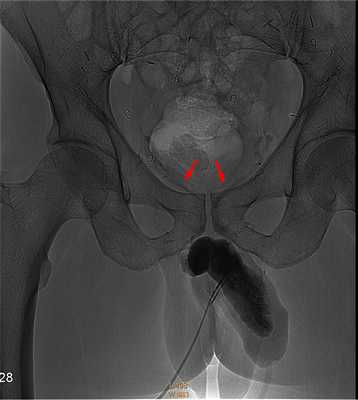

Кавернозография

Динамическая кавернозография - это диагностический тест, направленный на изучение причин веногенной эректильной дисфункции, и проводится при исключении других причин слабой потенции у молодых пациентов. Венозная утечка из эрегированного полового члена может развиться по разным причинам. Чаще всего это врождённое состояние или следствие тазовой венозной гипертензии (варикоцеле). При веногенной импотенции эрекция возникает, но она нестойкая, что не позволяет завершить половой акт. После выявления причин эректильной слабости у доктора появляется объект лечебного воздействия - несостоятельная вена, которую можно закрыть и улучшить эрекцию.

![Патологический венозный дренаж из члена]()

Ход исследования

В процессе подготовки к выполнению кавернозографии сначала проводится измерение давления в пещеристых телах. В расслабленный пенис через инъекционный насос вводится 60 мл физиологического раствора + 20 мл контрастного препарата со скоростью 0,4 мл / с. Через 10 минут наступает эрекция полового члена. С целью визуализации заполнения кавернозных тел с боковых и прямых проекций после введения контраста выполняются рентгеновские снимки. При достижении интракавернозного давления в 150 мм.рт.ст. нагнетание раствора уменьшали до 0,1 мл в секунду для поддержания хорошей эрекции. При снижении артериального давления в пещеристых телах выполняли кавернозографию на фоне увеличения скорости инфузии.

Такой метод имитировал естественную эрекцию, а её ослабление в процессе исследования позволяло выявить наличие различных патологических венозных сбросов. Такая кавернозография даёт достаточно информации о венозных утечках, однако существует риск развития приапизма, а контрастирование дорсальной вены полового органа позволит определить эти утечки без необходимости интракавернозных инъекций. Однако прямая кавернозография необходима для выявления изменений органической структуры пениса при болезни Пейрони и разрывов в кавернозных телах.